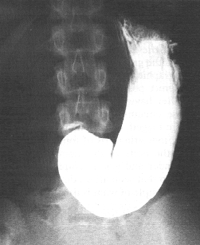

Case 26.1. G.C., male aged 24 years, was referred for barium study because of vague upper gastrointestinal symptoms. Having swallowed the first 3 mouthfuls of barium, the patient complained of feeling nauseous; there was no retching but he was unable to continue drinking. Initially the stomach appeared to have a normal tone, but the greater curvature sagged, moderate gastric dilatation occurred and peristaltic activity and cyclical contractions of the pyloric sphincteric cylinder ceased. A trickle of barium had entered the duodenal bulb but no further gastric emptying occurred (Fig. 26.1). He was advised to sit down. After 15 minutes the nausea disappeared and the examination could be resumed. Gastric tone, peristalsis, sphincteric cylinder activity and emptying became normal; no organic lesion was detected.

| Fig. 26.1. Case G.C. Moderate dilatation of stomach, sagging of greater curvature, and absence of peristalsis and cyclical activity of pyloric sphincteric cylinder |